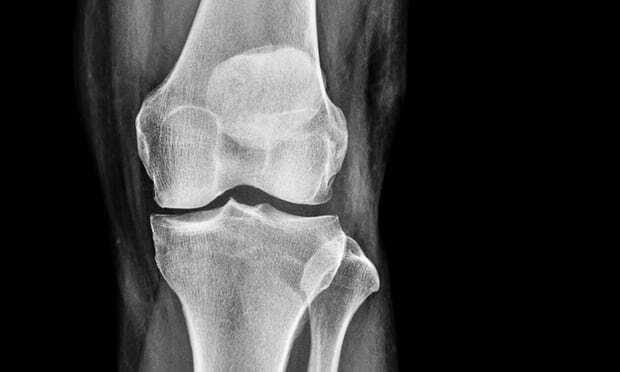

Loãng xương là bệnh dễ gặp phải nhưng hầu như không được quan tâm, có 7 cách đơn giản để chăm sóc sức khỏe của xương giúp bạn luôn khỏe mạnh, cứng cáp ngay cả khi cao tuổi về già.